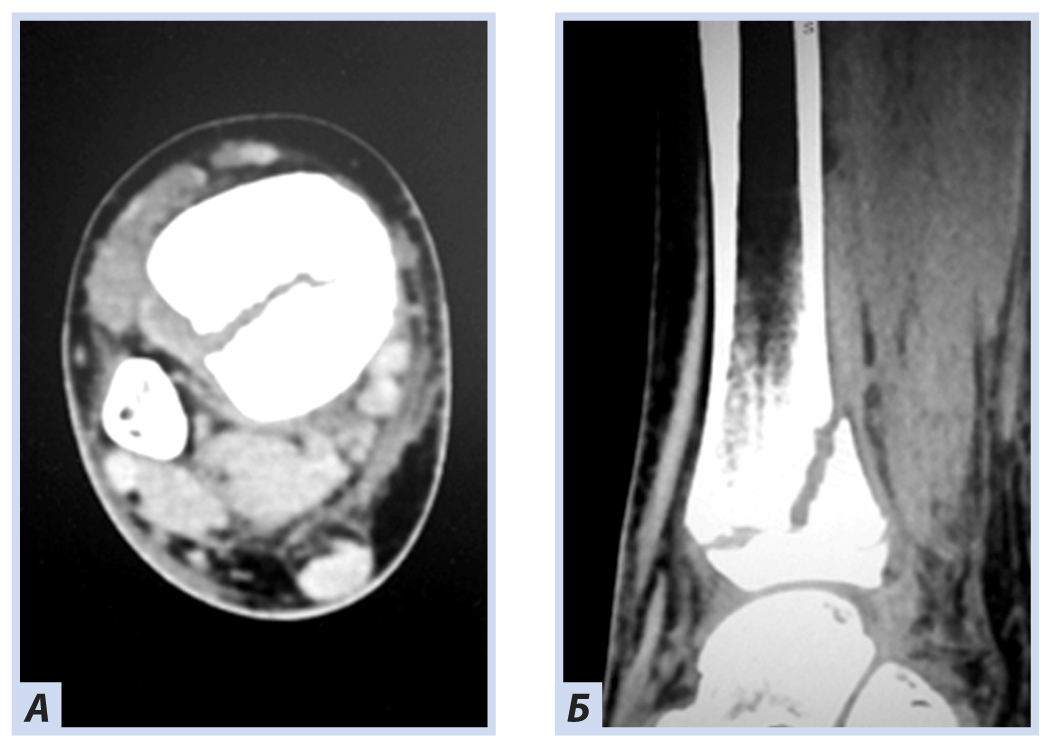

Клиническое наблюдение 1

Девочка, 10 лет, диагноз: «Закрытый дистальный остеоэпифизеолиз правой большеберцовой кости, Salter–Harris, II тип». Травму получила, упав с самоката, вследствие чрезмерного сгибания стопы кзади. По механизму травмы — ротационно-флексионный перелом дистального отдела костей голени. По данным компьютерной томографии выявлена значительная степень (5 мм) смещения отломков. Учитывая возраст больной, остеосинтез выполнен закрыто перекрещивающимися спицами. Дополнительная иммобилизация осуществлялась в задней гипсовой лонгете до коленного сустава. Контрольные рентгенограммы выполняли через 4 и 6 нед. после репозиции. Спицы удалены через 6 нед., конфигурация сустава восстановлена полностью (рис. 1–5).

Рис. 2. Тот же пациент. Компьютерная томография дистального отдела костей голени. Дистальный остеоэпифизеолиз правой большеберцовой кости: А — горизонтальная плоскость; Б — саггитальная плоскость.